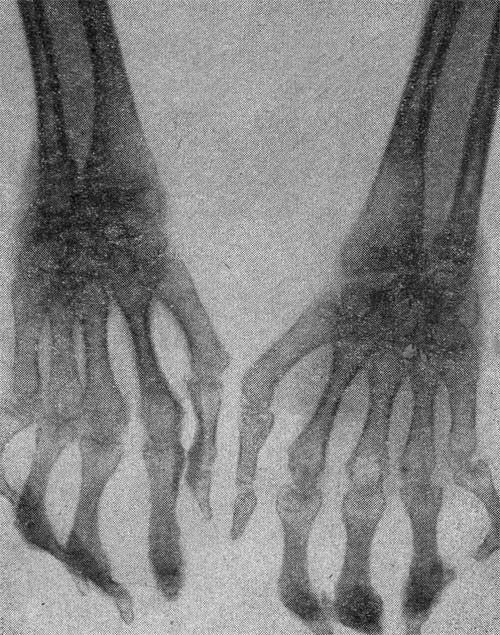

Множественные анкилозы, подвывихи, кистевидные просветления

Со стороны пальцев стоп наиболее типичны hallus valgus и контрактуры пальцев («птичья лапа»). Из 300 наблюдавшихся нами детей подвывихи и вывихи констатированы у 40 (15%), т. е. реже, чем у взрослых. Наблюдались в основном подвывихи в пястно-фаланговых суставах кисти с ульнарной девиацией — у 12 больных (4%), у 5 больных отмечен подвывих в лучезапястном суставе, у 4 — в межфаланговом суставе большого пальца, у 5 — в голеностопном суставе и суставах стоп, у 7 — в коленном, у 5 — в тазобедренном и у одного — в плечевом суставе.